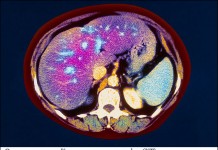

Печеночная недостаточность возникает, когда значительная часть ткани печени повреждена, и орган не может больше нормально функционировать. Это страшное заболевание способно убить за два дня....